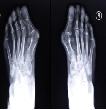

Figure 2 : Radiographie de face de l’avant pied en charge Hallux Valgus

Une radiographie du pied et de l’avant-pied en charge (face, profil et incidence de Méary) permet d’évaluer :

-L’angle de déformation (angle entre le premier métatarse et

la première phalange de l’hallux)

-L’angle entre le premier et le deuxième métatarse (angle M1-M2)

-Les répercussions sur les métatarsiens

-Les déformations secondaires

-Les éventuels troubles de la statique de l’arrière-pied qui peuvent favoriser ou aggraver l’Hallux Valgus (pied plat, etc)